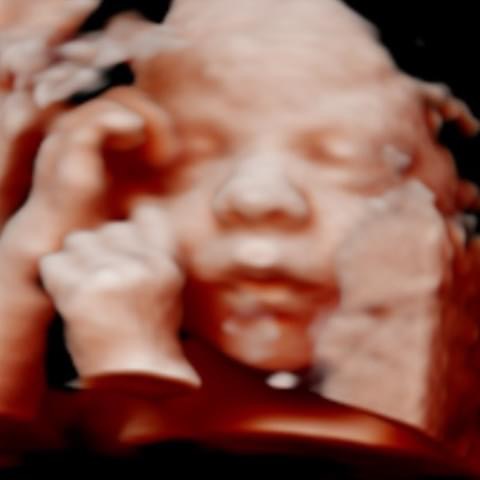

All photos are from our equipment and are of our actual clients.